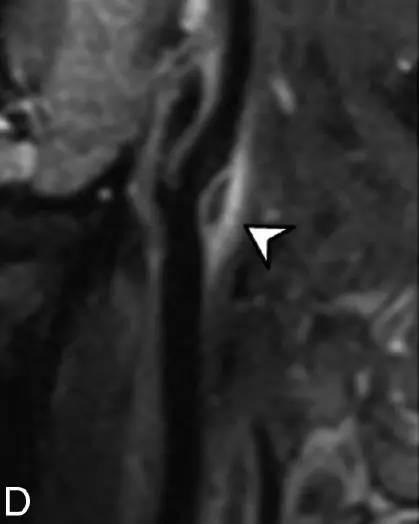

例4:增强前(图A)和增强后(图B)脂肪抑制3D T1 以及3D T2加权(图C)MRI显示颈动脉分叉处短T1和长T2血管周围浸润(短箭头),可见强化。颈动脉后部可见内膜软斑(长箭头)。右侧ICA矢状位曲面重构增强T1(图D)显示右侧颈动脉分叉以及颈总动脉末端和颈内动脉近端可见血管周围浸润(短箭头)。颈总动脉和颈内动脉其他部分未见血管或血管周围异常信号。